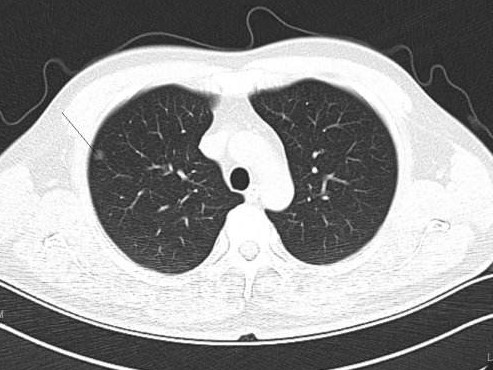

肺部结节如果属于肺癌,有以下几种特征:

1. 毛刺:肺部结节周围呈现短毛刺状,类似于太阳周围的毫光,密集且较为均匀,需警惕肺癌的可能性。

2. 密度:一般来说,纯磨玻璃结节相对于实性结节恶性的概率较大;混合型磨玻璃结节密度相对于磨玻璃结节高一些,其中纯磨玻璃结节密度最低。

3. 分叶:若结节呈现非常均匀的圆形团块状,大部分为良性结节;若结节表面凸凹不平,类似不规则的土豆,恶性的概率较高。

4. 分界:结节与周围正常肺组织分界不清,恶性的概率较大。

5. 空泡:结节中央有空泡,相对于没有空泡的结节,恶性的概率较高。

6. 胸膜牵拉或胸膜凹陷征:这是恶性表现之一。